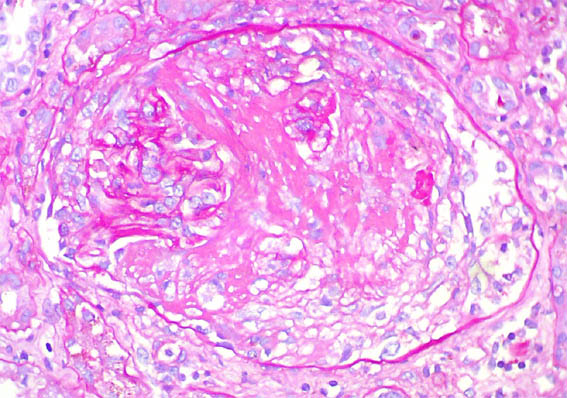

Figura 1. H&E, X100.